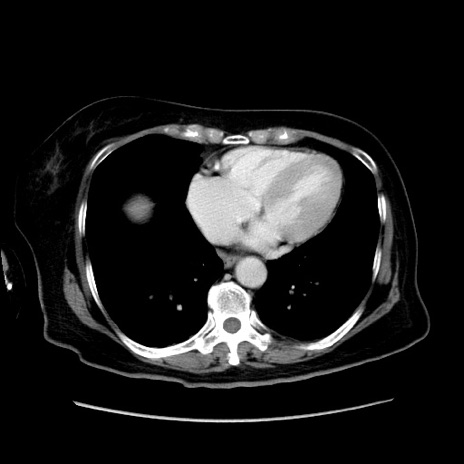

症例19(横断像)

【症例】80歳代女性

【主訴】下腹部痛

【現病歴】約8時間前より下腹部痛の出現あり、救急外来受診。

【既往歴】両側付属器切除

【身体所見】意識清明、下腹部正中に手術痕あり、その部位に一致して圧痛と反跳痛あり。腸蠕動音は亢進。

【データ】WBC 9300、CRP 0.15